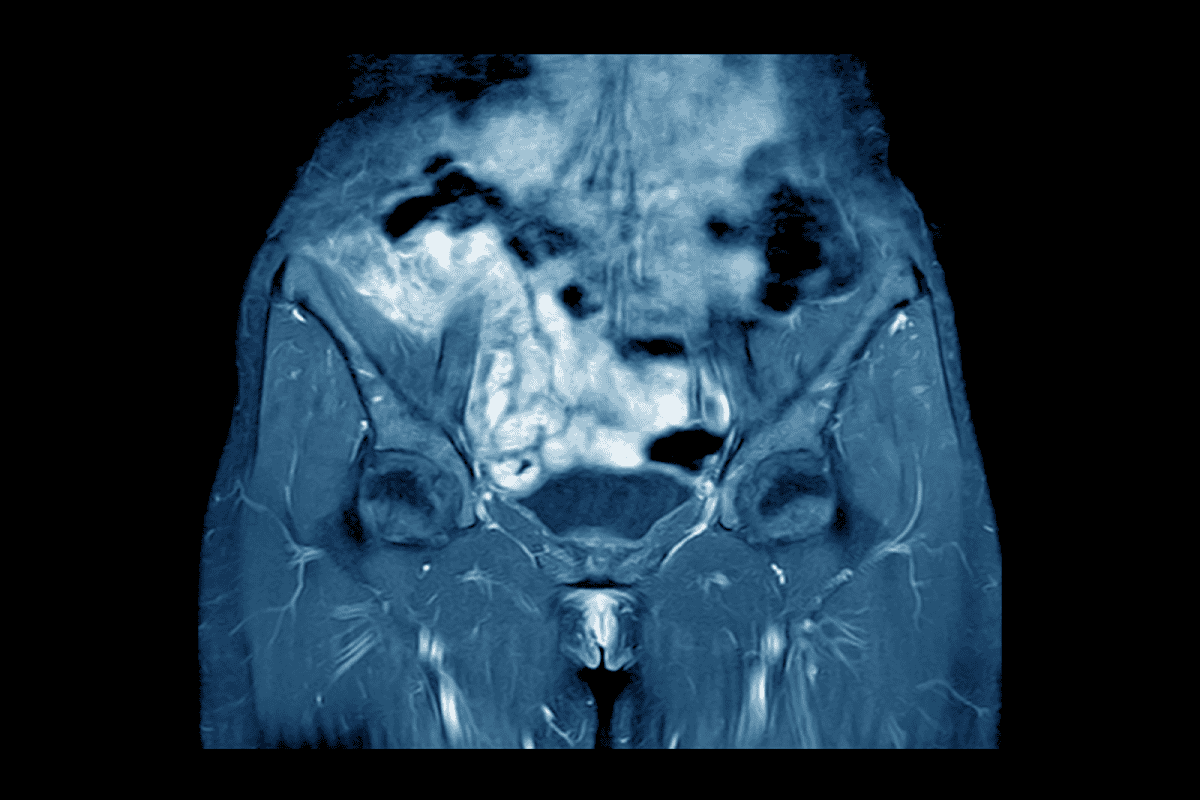

- Ecografía de cadera: se pretende diagnosticar si hay derrame articular (líquido dentro de la cápsula de la articulación). Esta ecografía nos sirve para confirmar la inflamación y ayuda a medir la cantidad de líquido. Si hay duda sobre el cuadro clínico y hay mucho líquido, la ecografía puede guiar una punción para analizar dicho líquido.